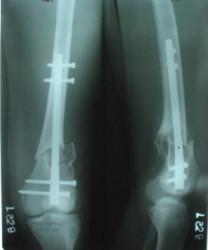

Отправитель: V. M. Iyer 28 Декабрь 2003, 20:25

1

Alex>>Since one of nail ends has to be locked without targeting device i

Alex.>> prefer this to be the distal end.

In the supracondylar nail system both the ends are lockable by jig and no free hand technique is needed.

Alex>> Than in the presented case?

I do not see the proximal bolts; I presume they must be at he trochanter level. In a supracondylar nail you are able to see both side bolts in one picture. ( Enclosure)

[ Ответить ]